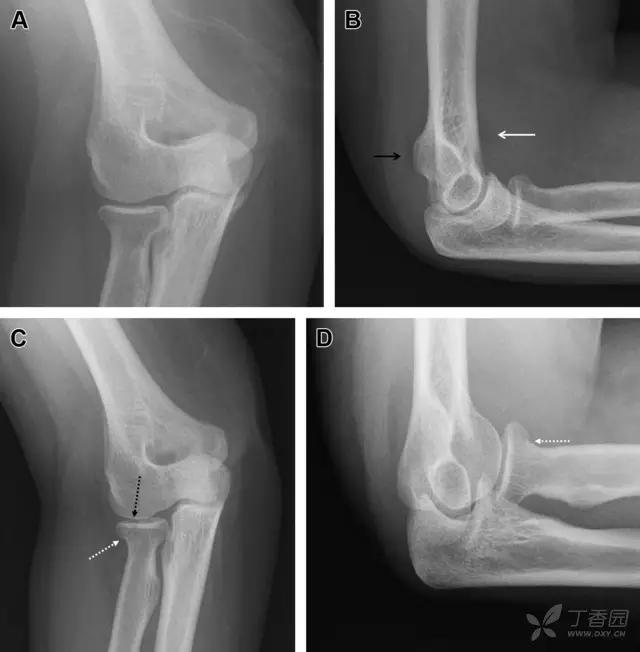

24 无移位的桡骨头/颈骨折

多发生于摔倒时,手掌撑地,受到轴向、外翻应力所致。常规的前后位片容易漏诊,常需加拍内斜位、外斜位、桡骨头-肱骨小头位片。后脂肪垫可见(位于鹰嘴窝内,一般不可见)和/或前脂肪垫抬高常提示骨性损伤。

图 2 桡骨头骨折。前后位(A)和侧位(B)片示后脂肪垫抬高(黑色箭头),前脂肪垫抬高(白色箭头),呈「帆船征」,其它表现正常;外斜位(C)和桡骨头–肱骨小头位(D)示桡骨头关节内骨折线(虚线黑箭头)累及桡骨颈(虚线白箭头)